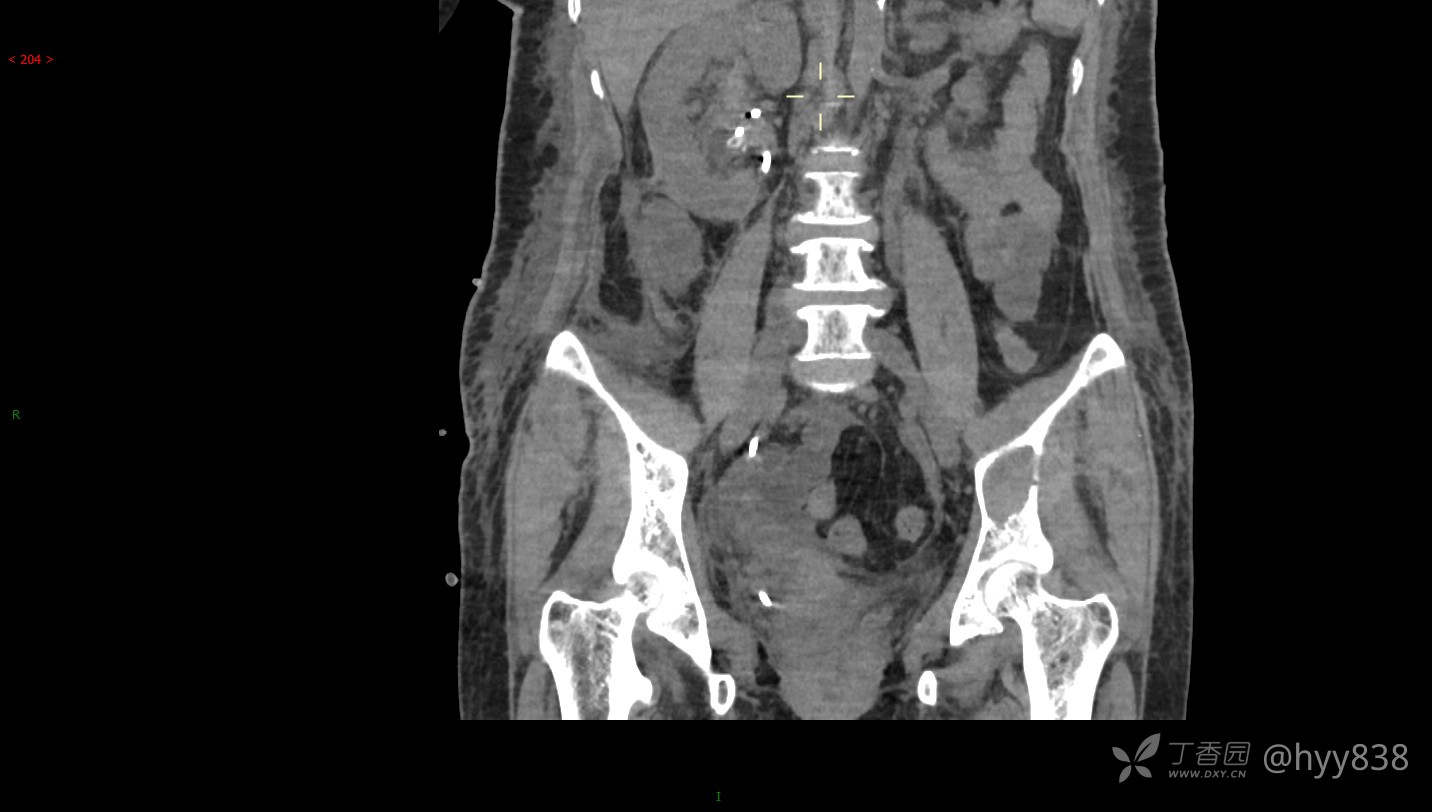

CT平扫